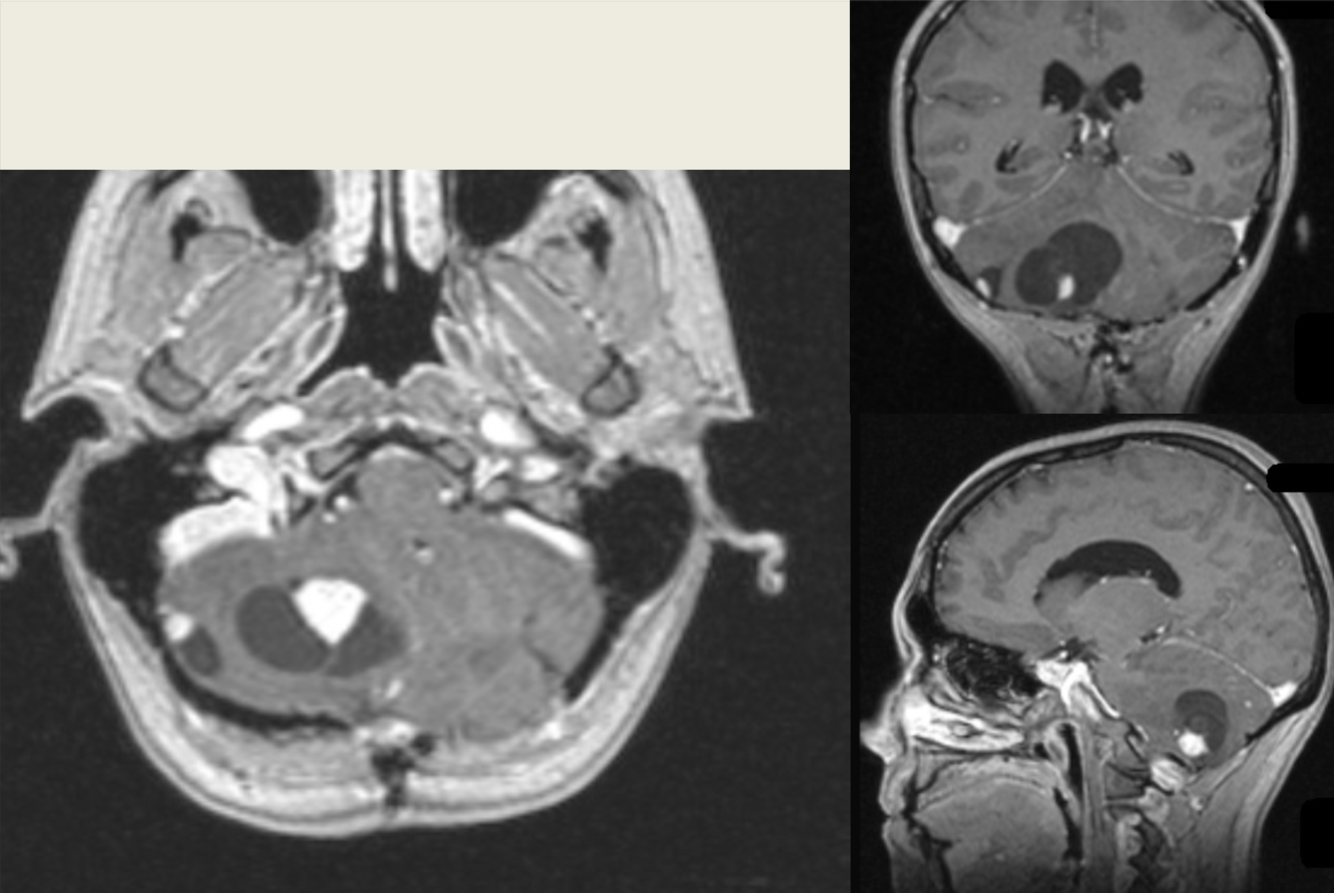

13 y/o with ataxia.

Von-Hippel-Lindau syndrome with cerebellar hemangioblastomas